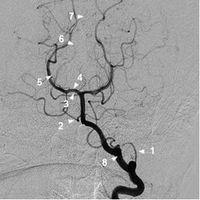

椎动脉造影

椎动脉

椎动脉分段示意图

椎动脉分支解剖图

椎动脉分段解剖图

椎动脉解剖图

椎动脉5段法解剖图

椎动脉图片解剖

椎动脉图片